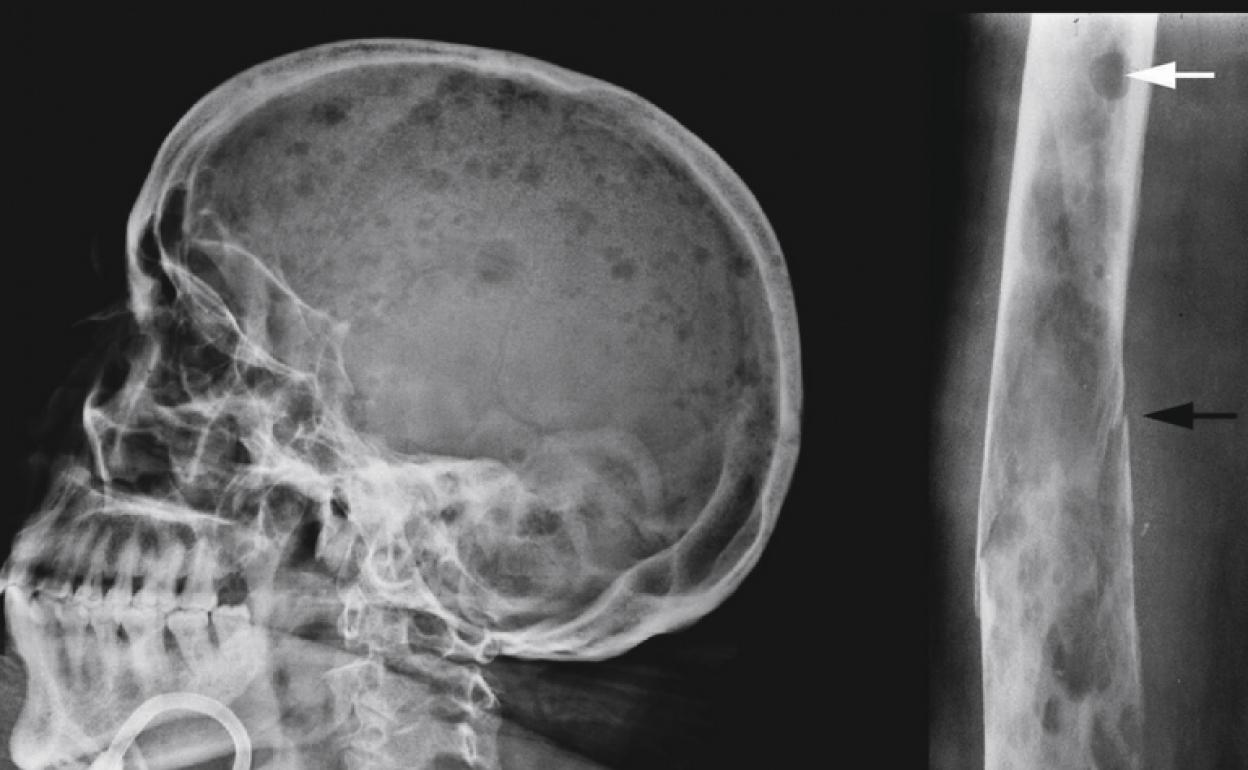

Cada año se diagnostica a dos mil personas con mieloma múltiple. Un singular tipo de cáncer, incurable, que a sus duros efectos físicos añade un dolor emocional más: su desconocimiento por la sociedad. «¿Tienes un melanoma?», es la respuesta habitual que estos enfermos reciben al enunciar lo que padecen. Pero no, no es un cáncer de piel.El mieloma es un cáncer de la médula ósea que acaba 'comiéndose' los huesos. Es difícil de diagnosticar.

Uno de los problemas anímicos de este cáncer es el hecho de que se pase por varios periodos de remisión y recaída. El temor a su reaparición tiñe de angustia la vida de los pacientes. Además, lógicamente, del difícil día a día, en el que la debilidad ósea puede hacer que te rompas el brazo con solo abrir una puerta.